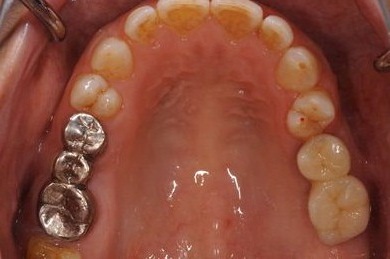

| 性別/年齢 | 女性 / 59歳 | ||||||||||||||||||||||||||||||||

| 治療方針 | 左上奥ソケットリフトにて上顎洞を拳上、骨再生法を行い、インプラント治療を可能にする。 | ||||||||||||||||||||||||||||||||

| 治療内容 | インプラント4本(GBR)、ハイブリッドセラミック4本 | ||||||||||||||||||||||||||||||||